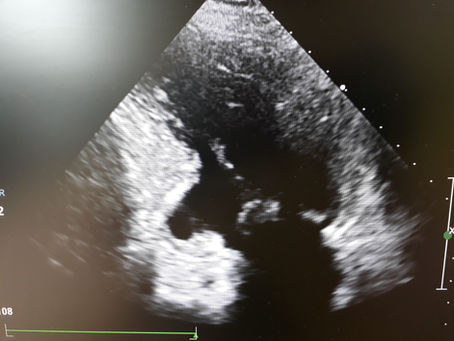

L'infarto c'e' stato e si vede..

Nell'immagine sotto si puo' vedere la cicatrice di un infarto pregresso: vedete quella rientranza in basso a sinistra? In quell'area...